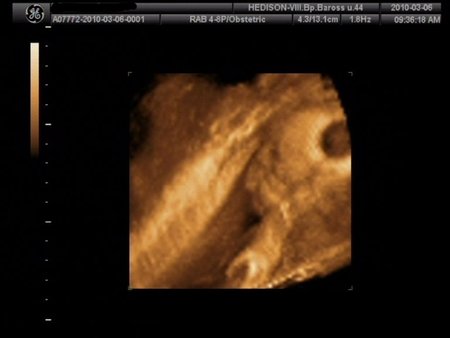

Móni, nem is igaz. Profilból is látszik, hogy nagyon édes ez a kislegény.

Szép kis pofija lesz nagyon! Na, mindjárt vissza is megyek, csodálom még kicsit.

Hú, ez az egy kiló is nagyon jó érték ám. Amikor én kórházban voltam 27 hetesen, akkor született egy kicsiny fiúcska, 27 hetesen volt 900 g.